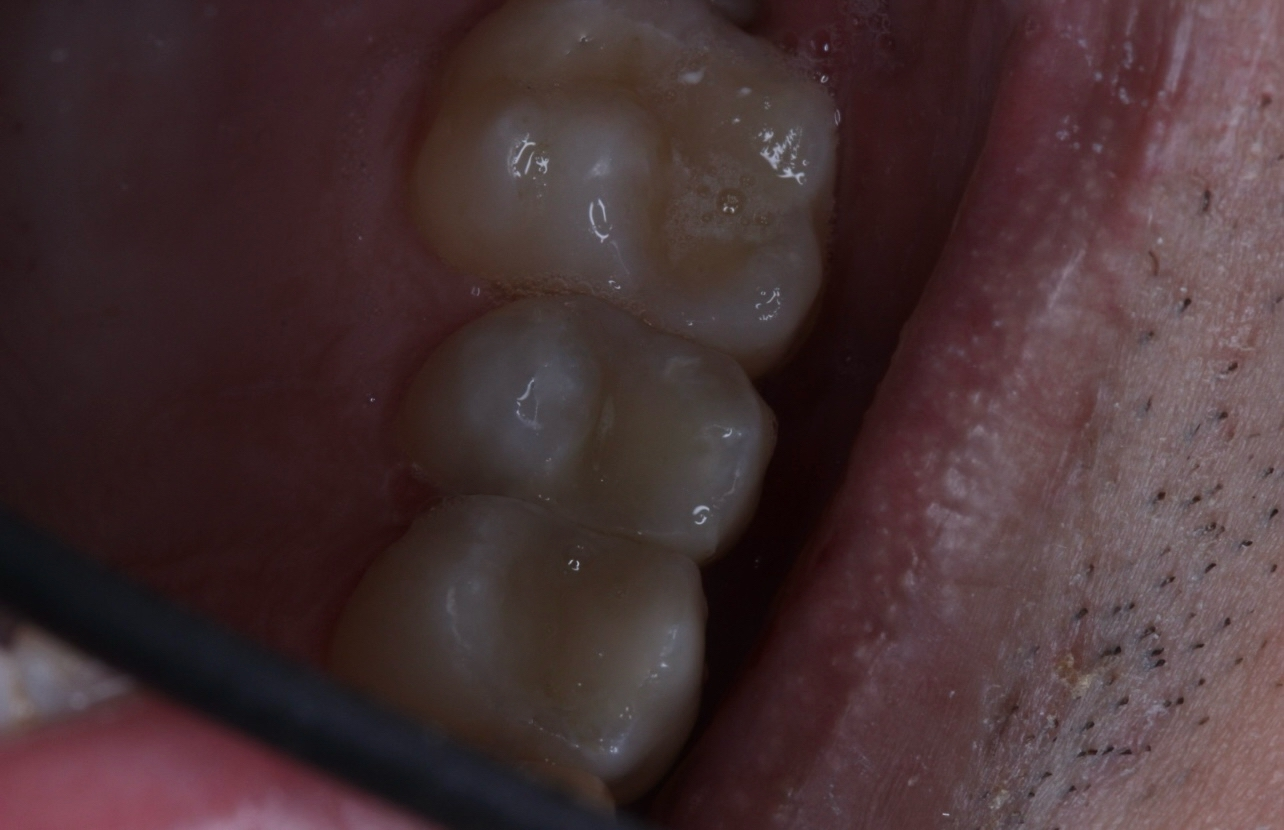

Нервы в зубах или мои? Если мои, то наверное да.. в санаторий меня срочно

Аноним 09/03/26 Пнд 18:12:23 1661593 261